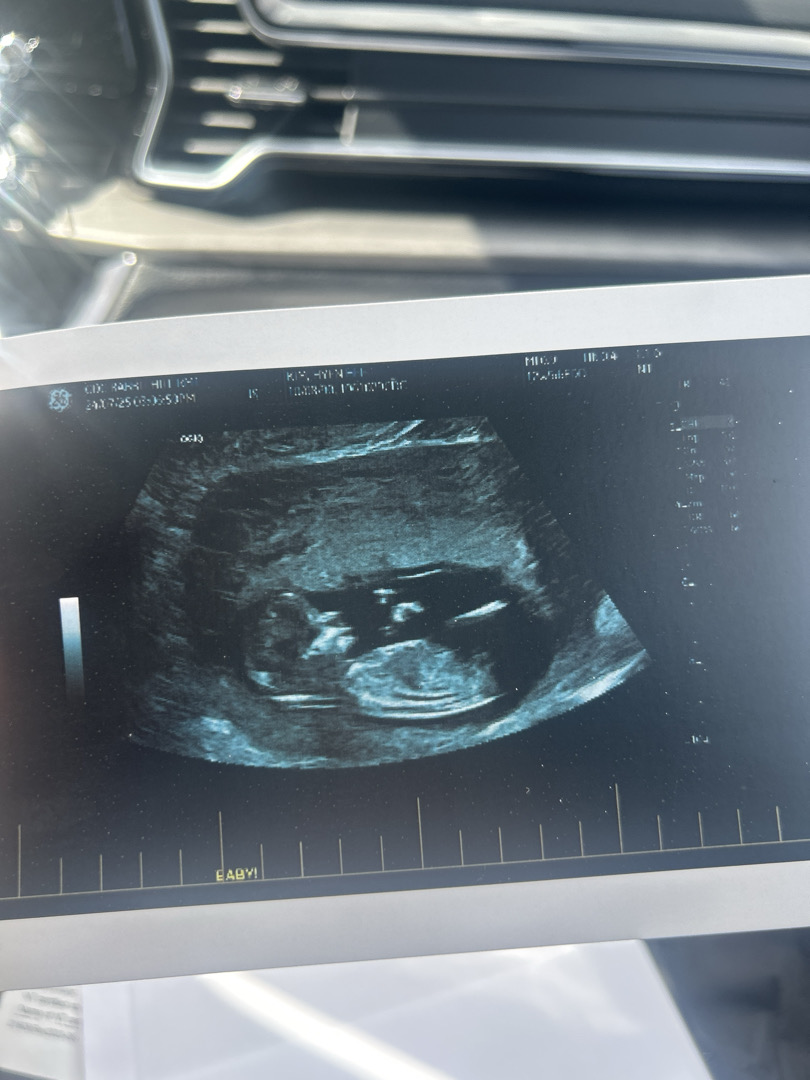

이 사진으로도 각도법을 볼수 있나요??

12주 5일 차인데 아들인지 딸인지 각도 법 한번 봐주세요!!